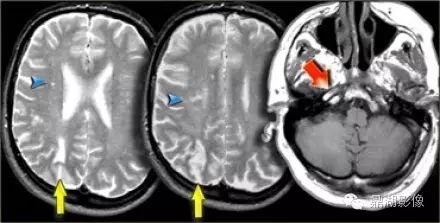

小脑上动脉梗塞

65fad851087608397671532d353a4d7b.jpg

大脑前动脉梗塞

A1:起始部—前交通动脉,发出内侧豆纹动脉,供应尾状核头部和内囊前肢

A2:前交通动脉——胼周动脉——胼缘动脉

A3:皮层支

8be3878cf56b252dfbde23d2cdff9e4f.jpg

脉络膜前动脉梗塞

脉络膜前动脉由颈内动脉发出,供应海马,内囊后肢及其外侧

d4a074e938e451b8a6672cf3a2243eaa.jpg